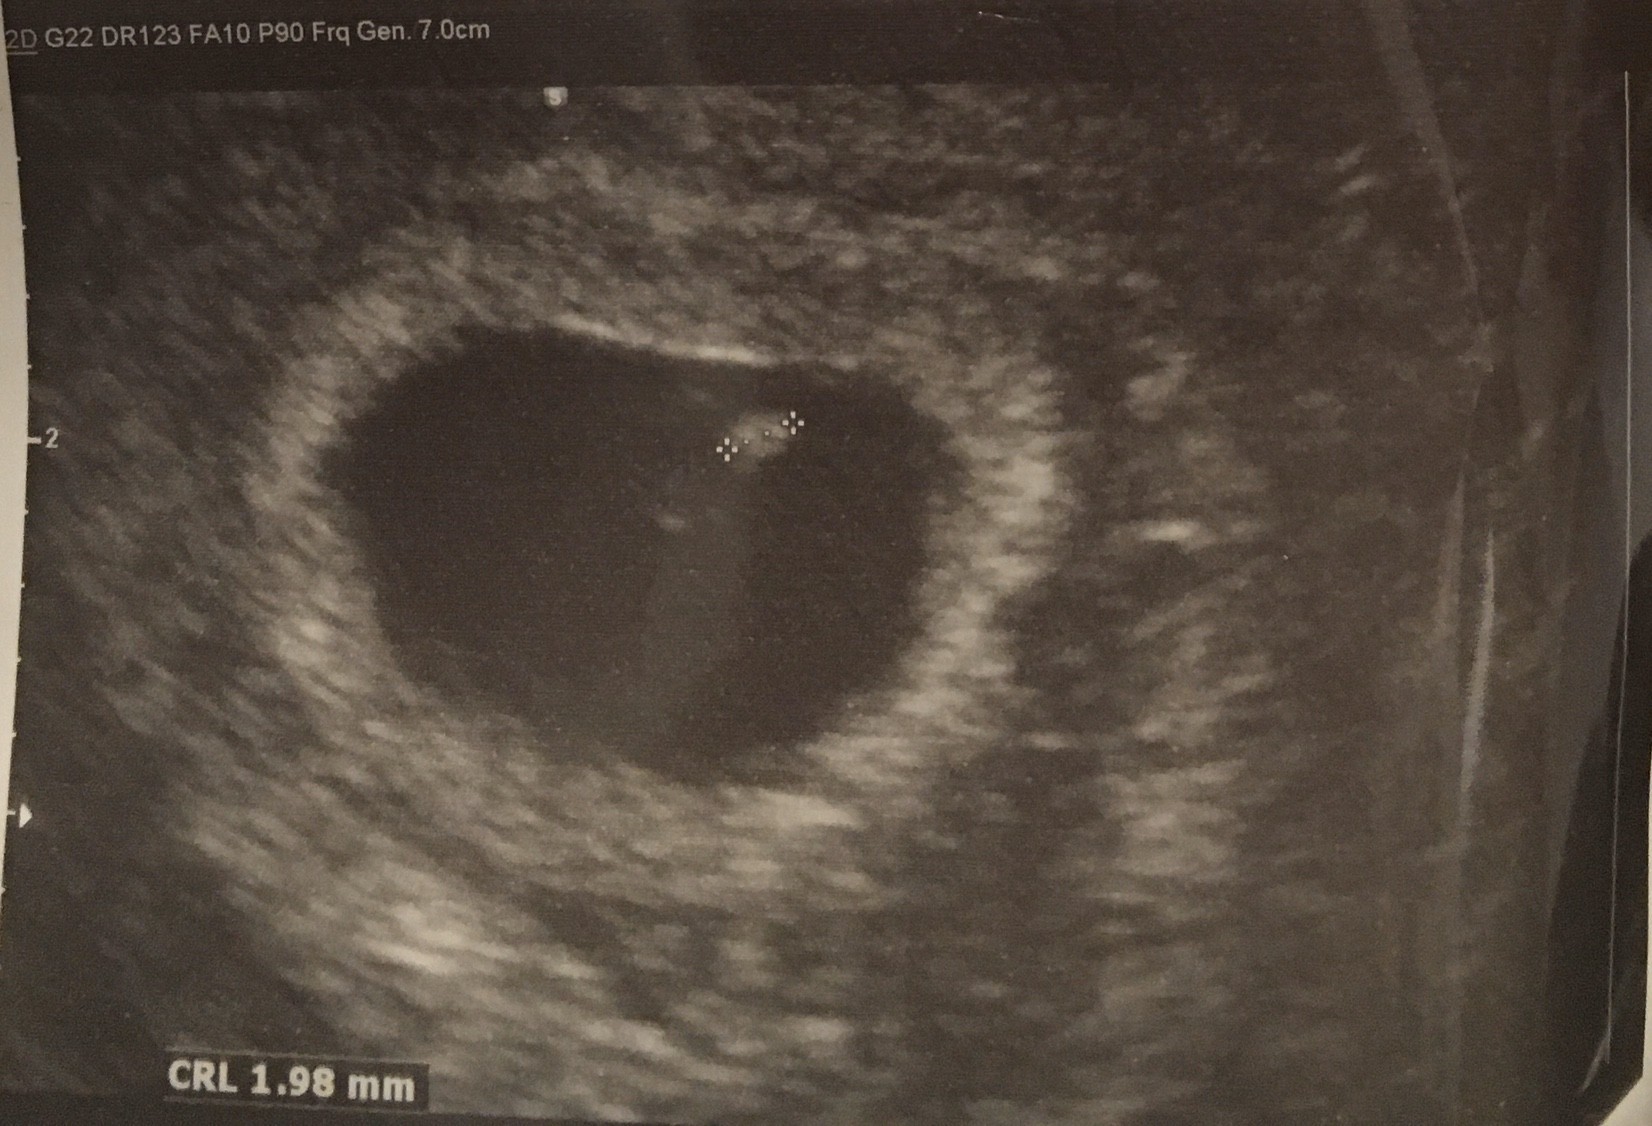

Chciałam żeby miał Pamiątkę i zapisałam się na prywatne usg ciąża młodsza niż w apce ale to wszystko będzie się wyrównywać. Słyszałam serduszko mam fotki dla męża także dziec zaczęłam super [emoji7] miłego dnia dla was

Chciałam żeby miał Pamiątkę i zapisałam się na prywatne usg ciąża młodsza niż w apce ale to wszystko będzie się wyrównywać. Słyszałam serduszko mam fotki dla męża także dziec zaczęłam super [emoji7] miłego dnia dla was Zobacz załącznik 1078409Zobacz załącznik 1078410